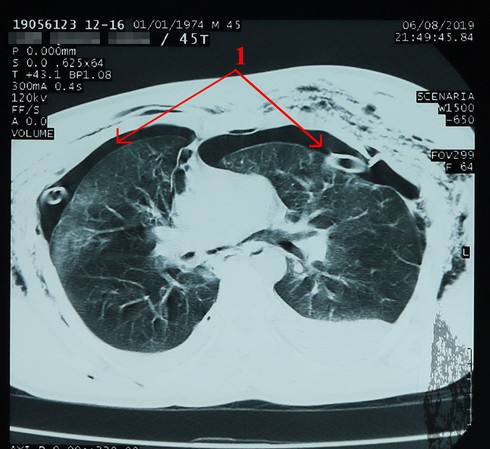

Phần tràn máu, tràn khí mảng phổi 2 bên trên phim chụp X.Quang (phần màu đen hướng mũi tên) |

Theo các bác sĩ của Bệnh viện cho biết, người bệnh nhập viện trong tình trạng đau, tức ngực nhiều, khó thở, trầy da, bầm tím vùng ngực, lồng ngực 2 bên mất cân đối, có dấu hiệu của mảng sườn di động. Trên phim chụp X.quang và CT.Scanner cho thấy người bệnh H. bị gãy nhiều xương sườn 2 bên: từ xương số 2 đến xương số 9 bên phải và từ xương số 1 đến xương số 7 bên trái; gãy xương đòn phải, xương bả vai phải; tràn máu, tràn khí màng phổi 2 bên.